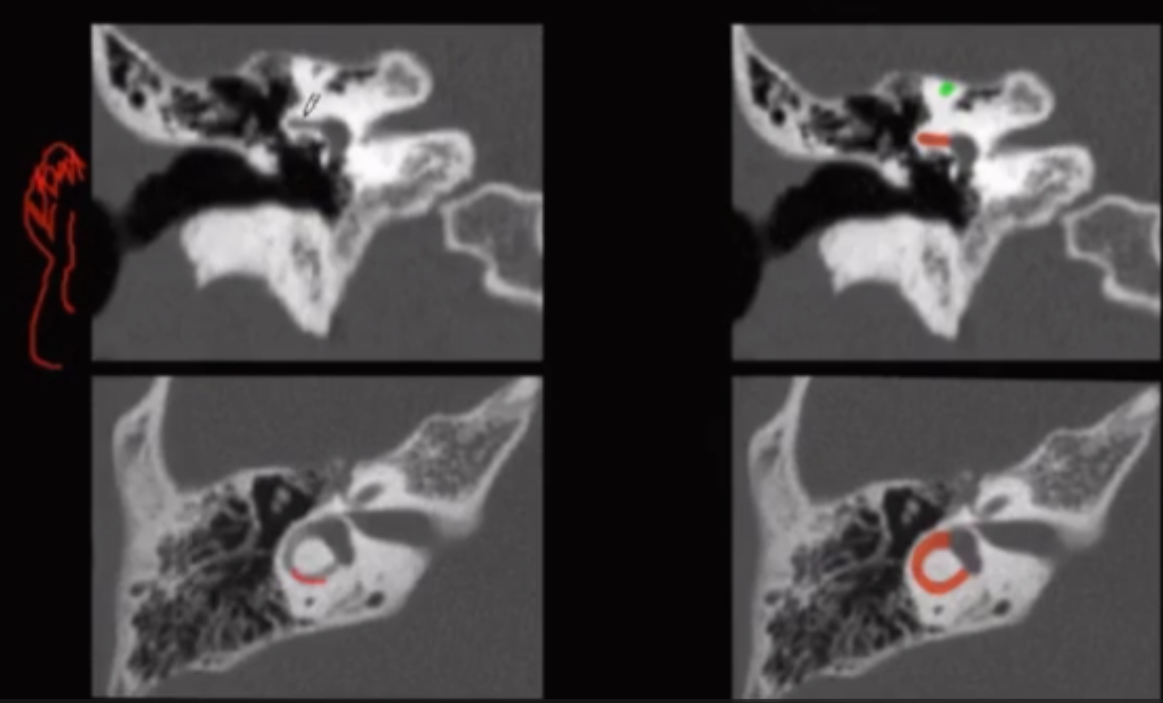

• Glomus tympanicum

• Superior to jugular foramen (t-bone lesion)

• Occurs only in the middle ear

• Jacobson’s nerve = tympanic branch of CN 9

• Located at cochlear promontory where this shit arises

• Glomus jugulare (image below tympanicum pic)

• Occurs only in the jugular foramen

• Permeative destruction of adjacent bone, looks like its eaten at

• Lateral semi-circular canal (red semi circle in image below) will be the first affected by cholesteatoma